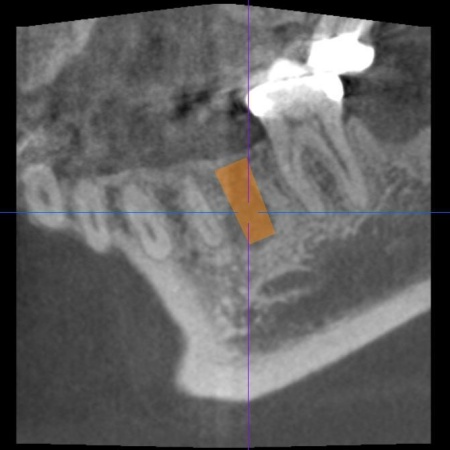

続いてインプラント手術を実施し、インプラントを正しい位置と角度で顎の骨に埋め込みました。

インプラント手術後は経過観察を行い、インプラントが顎の骨に結合したことを確認したら、インプラント上部に取り付ける人工歯を作製するために精密な型取りを実施します。